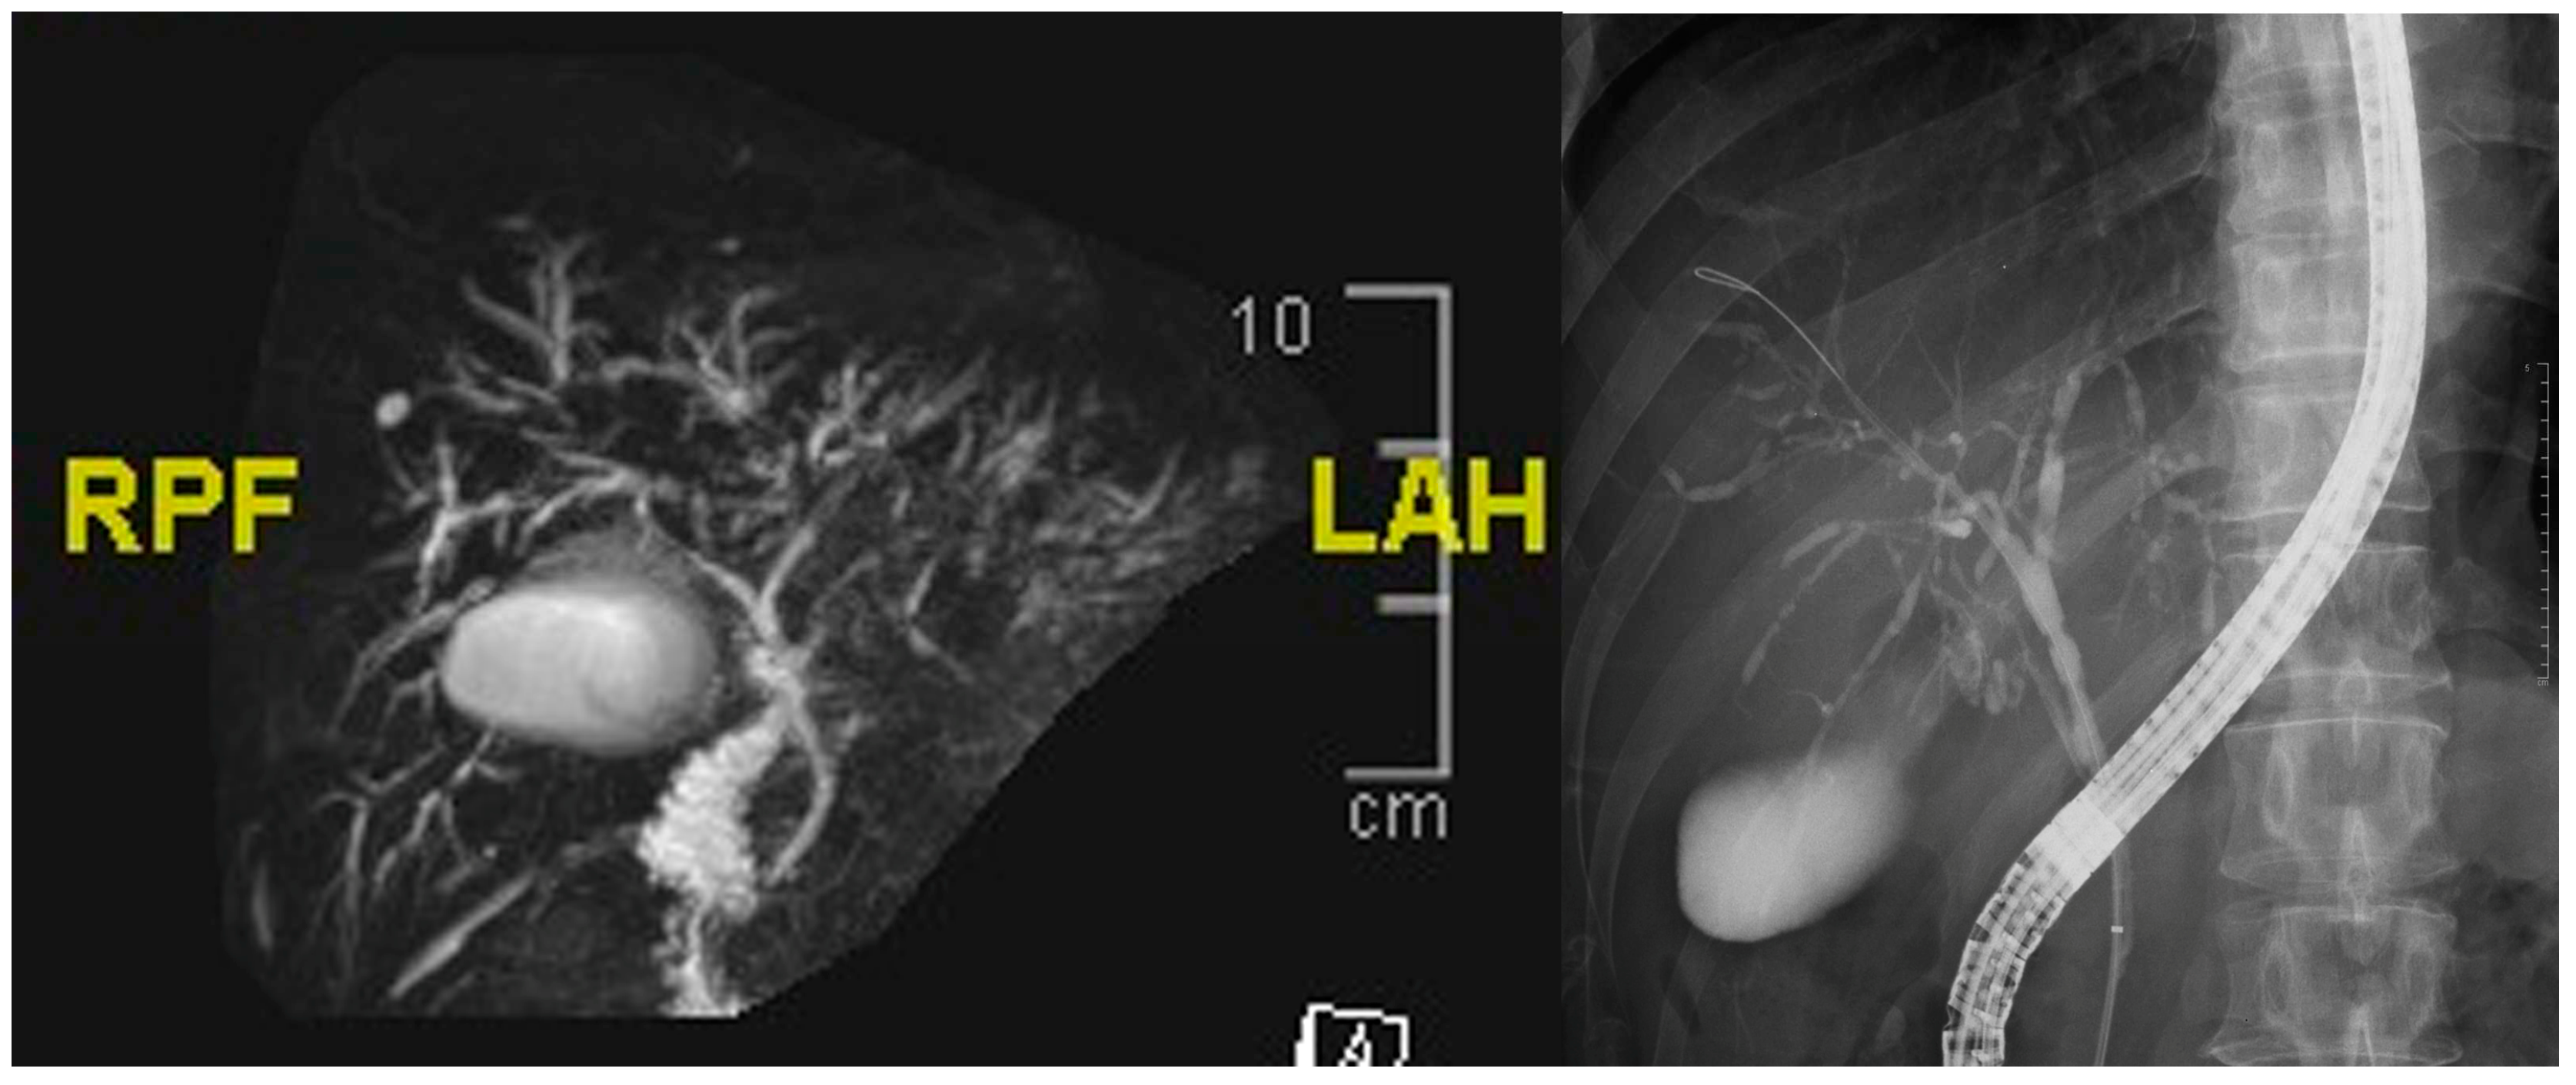

This 59-year-old man suffered from epigastralgia and progressive jaundice for 2 weeks. Tri-phase computer tomography showed diffuse dilatation of intrahepatic ducts (IHDs) with tapering at the hilum (Figure 1). Magnetic Resonance Cholangiopancreatography (MRCP) disclosed diffuse irregular sausage-like IHDs with minimal peri-ductal enhancement and endoscopic retrograde cholangiopancreaticography confirmed a hilar biliary stricture (Figure 2). The SpyGlass™ Direct Visualization System-II (Boston Scientific, Marlborough, MA, USA) demonstrated fibrinous exudates within an ulcerated and erythematous stenotic bile duct. No irregular dilated vessels nor papillary projections were noted, favoring a benign mucosa (Figure 3). POCS-directed biopsy reported chronic inflammation with negative CK AE1/3 staining. Following a 2-month course of ursodeoxycholic acid (15mg/kg/day) for PSC, the patient’s cholestatic-type jaundice normalized. During a three-year follow-up, the patient has been free from recurrent jaundice, cholangitis, and abdominal pain. Notably, both total bilirubin and alkaline phosphatase levels have consistently remained within the normal range, and serial MRCP scans have shown stable results (Figure 4).

Figure 2. On the representative MRCP image (left), there is diffuse sausage-like irregularity, with both narrowing and dilatation of the IHDs. Minimal peri-ductal enhancement is suggestive of cholangitis. The cholangiographic findings (right) reveal multiple skipped strictures affecting bilateral intrahepatic ducts, extending from the proximal common bile duct.